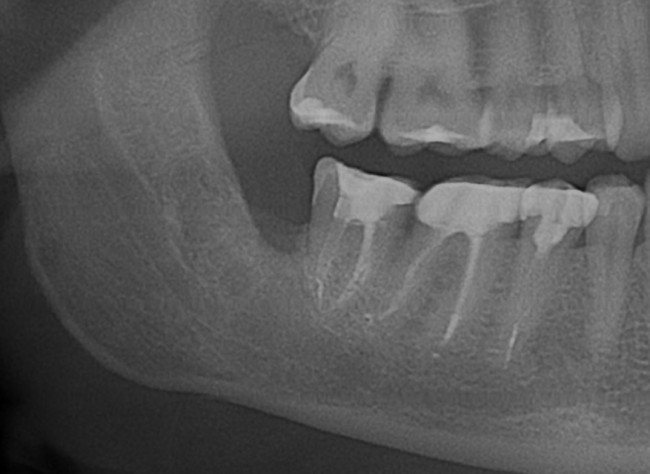

К нам в клинику обратился молодой человек с целью плановой санации: почистить зубной налет, вылечить кариес и т. д. Перед лечением ему сделали панорамный снимок. На снимке вот это:

Напомню, он пришел с целью плановой санации, а это значит, что ни зуб мудрости, ни киста. ни что-то там еще его не беспокоят. А теперь, внимание, вопрос ко всем вам:

— Нужно ли удалять зуб мудрости?

Следуя логике некоторых из моих коллег, а именно «если не беспокоит — не трогать«, этот зуб мудрости и кисту удалять не нужно. Не беспокоит же! Вот когда заболит, тогда придете! Слышали такие рекомендации? Я тоже слышал, причем неоднократно. Причем, от очень «авторитетных» (кавычки неспроста) специалистов.

Вернусь к нашему клиническому случаю. Да, ни зуб мудрости, ни киста, которая из-за него возникла, нашего пациента не беспокоят. Тем не менее, все вы видите явные показания к удаления и ретинированной восьмерки, и кисты.

Что мы и делаем. До удаления я попросил нашего терапевта Михайлову Елену депульпировать соседний седьмой зуб, поскольку, по данным КЛКТ, его корни выходили в просвет кисты. Жалко, конечно. Но вот, такие коварные эти зубы мудрости.